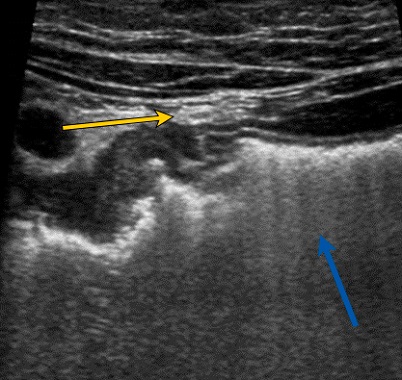

Se solicitó una ecografía abdominal, donde se objetivó un engrosamiento marcado de la pared duodenal y cambios inflamatorios yuxtaduodenales (Figs. 1 y 2). Además, se realizó analítica sanguínea y de orina, sin alteraciones; estudio microbiológico fecal negativo.

| Figura 1. Flecha azul: engrosamiento mural de la pared duodenal y cambios inflamatorios de la grasa adyacente. Flecha amarilla: adenopatía reactiva |